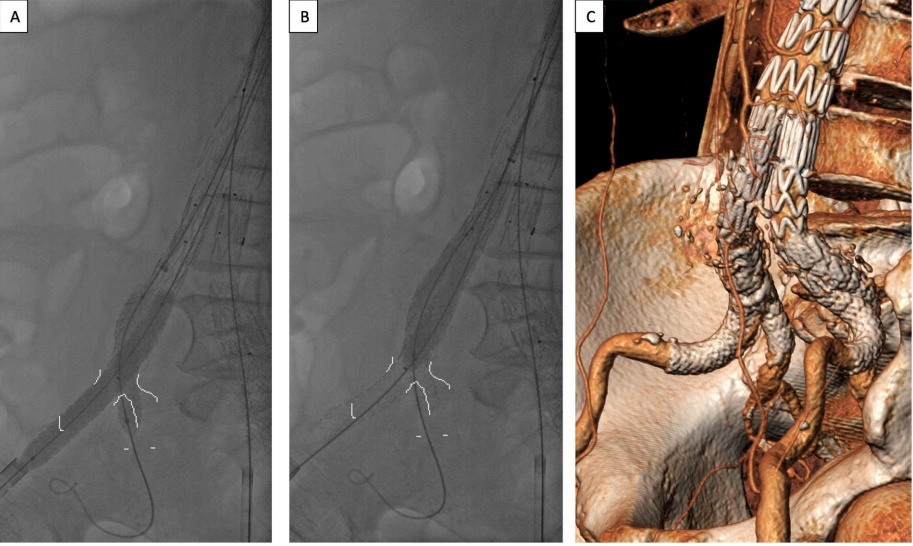

3.随后撤回鞘管,同时释放两个球扩覆膜支架(图2A)。展开后,回收IIA内覆膜支架的球囊,并将其推进EIA至髂支的近端,以高于额定压力的压力再次进行Kissing扩张(图2B),以便在髂支内形成更好的形状,降低任何内漏的风险(图2C)。在这个阶段,有时会使用更大直径的球囊以达到更好的成形效果。

图2